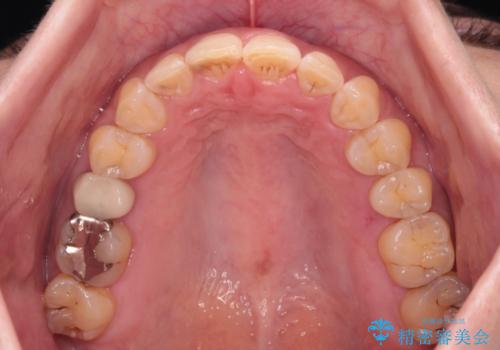

- 飛び出た上の前歯を気にして来院された患者様です。

奥歯の咬み合わせは、上顎歯列が理想的な一よりも数mm前方にある状態でした。

なるべく早めに治療を終えたいとのことで、補助装置を用いて上顎臼歯を後方に移動させ、同時にワイヤー装置にて整えることとしました。

舌の突出癖が原因で上下の歯に大きなスペースが生じていたため、舌のトレーニングをしっかり行っていただくことで、上顎歯列をスムーズに移動させることができました。